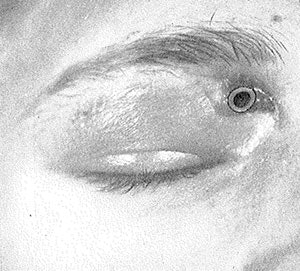

Office treatment of sinusitis in 1900 consisted of topical vasoconstriction (4 percent cocaine, 2 percent ephedrine); nasal washes with water, saline, or milk; and local heat. If these treatments were not successful for frontal sinusitis, trephination of the frontal sinus was performed via the intranasal infundibular route or, more commonly, through the bone of the orbital roof or the anterior sinus wall.

Persistent disease generally required highly destructive, disfiguring external surgeries such as those described by Kuhnt (1895) and Riedel (1898). More function-sparing transnasal procedures such as those described by Caldwell (1893) and Lothrop (1897) were rarely attempted.